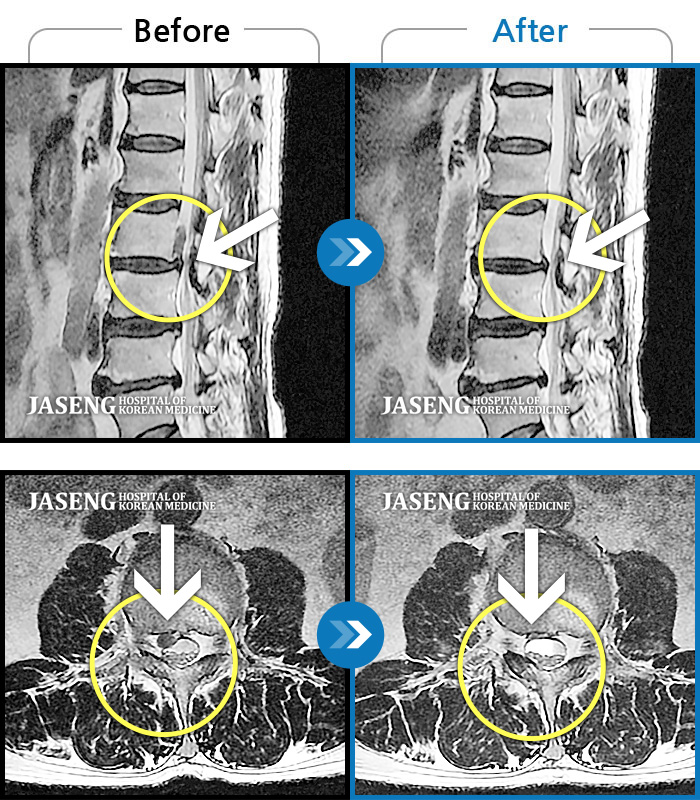

허리디스크

일산 · 배영현 교육수련부장

허리, 좌측 골반부터 좌측 다리로 통증 및 저림이 지속되고 좌측 다리의 감각이 둔함

촬영시기

2024.09.30 ~ 2025.11.25

2025.12.05